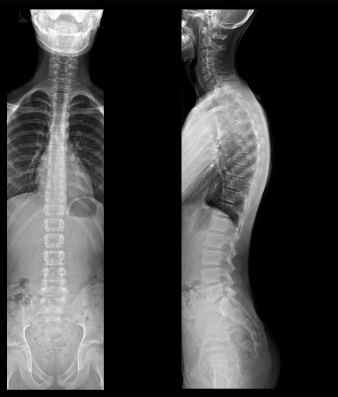

Wat kunnen we kenmerkend op Radiografie herkennen?

Bot

Waar treden de spinale zenuwen uit ter hoogte van de wervelkolom?

De spinale zenuwen verlaten het wervelkanaal via het foramen intervertebrale. In het cervicale gebied liggen de zenuwen meestal boven het corresponderend wervellichaam, terwijl vanaf thoracaal en lager ze onder het corresponderend wervellichaam uittreden.